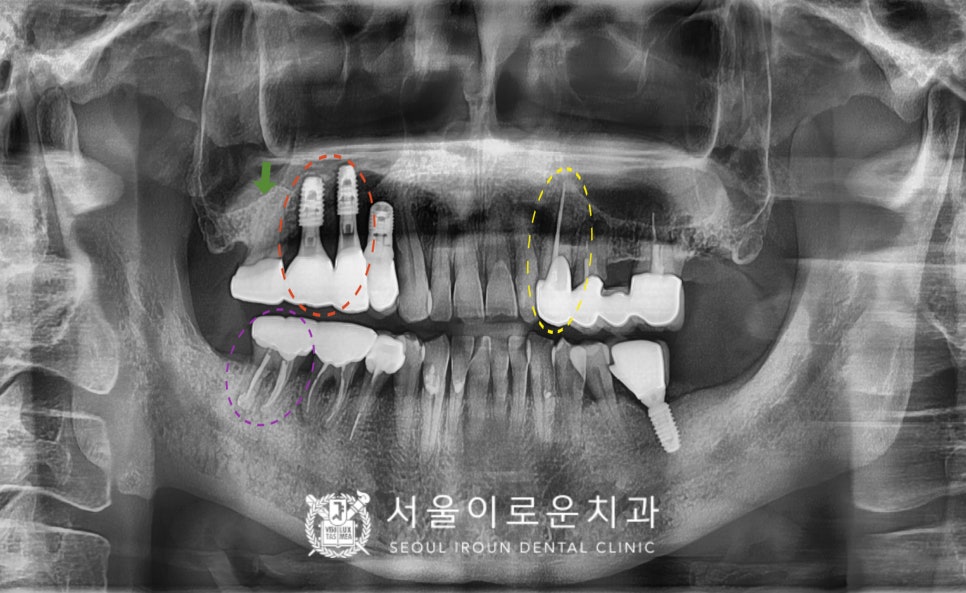

위턱 오른쪽의 임플란트가 잇몸뼈와

단단하게 결합되기를 기다리는 동안

위턱 왼쪽 송곳니(#23)의

크라운 제작을 위한

인상채득을 진행하였으며,

보철물은 자연치아와 강도가 가장 유사하고

심미적인 지르코니아 보철물로

진행을 도와드렸습니다.

그리고 임플란트 식립 후 4개월 뒤

osstell beacon이라는

골 유착을 확인할 수 있는 장비를 이용하여

isq를 측정하여

뼈와 임플란트가 잘 결합되었는지

안정 값을 확인한 뒤

보철 과정을 진행하였답니다.

그리고 바로 뒤에

위턱 오른쪽 두 번째 큰 어금니(#17)는

기본 크라운 제거 후 평가해 보았더니

살려 쓸 수 있다고 판단하여

임플란트와 같이 보철물 제작을 위한

인상채득을 진행하였습니다.

임플란트 / 크라운 수복

신경치료 후 크라운 수복을

모두 마무리 한 모습입니다.